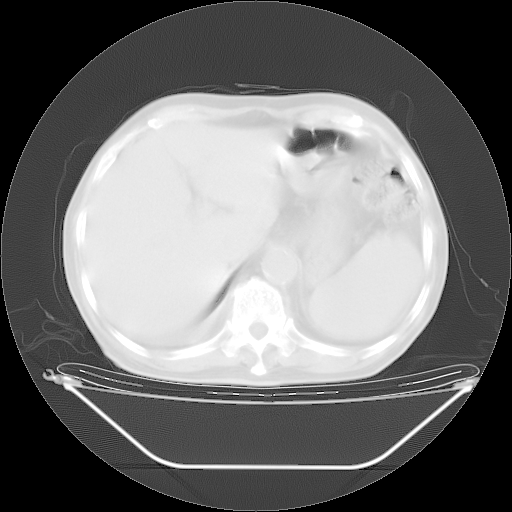

今天复查肺部CT,发现双肺广泛磨玻璃样改变。所以我把3月19日和5月9日相隔50天的肺部CT上传。请大家会诊。

5月9日肺部CT(在4月27日齐鲁医院肺部CT描述部分肺组织磨玻璃样改变,12天后肺组织广泛磨玻璃样改变)

2009年5月9日肺部CT

大致读了系列胸部CT:纵隔窗无明显异常,肺窗:从4、27至今:主要是双肺中下野外带可见毛玻璃样改变,目前处于急性肺泡炎阶段,至于原因考虑1、结替组织或胶原血管性疾病所致?2、恶性疾病如恶组在肺部所致的表现或细支气管肺泡癌?3、药物或其它原因如肺蛋白沉着症所致肺泡炎目前不太可能?总之,明天就去请我院的呼吸科、感染科、血液科和临免专家会诊哈。